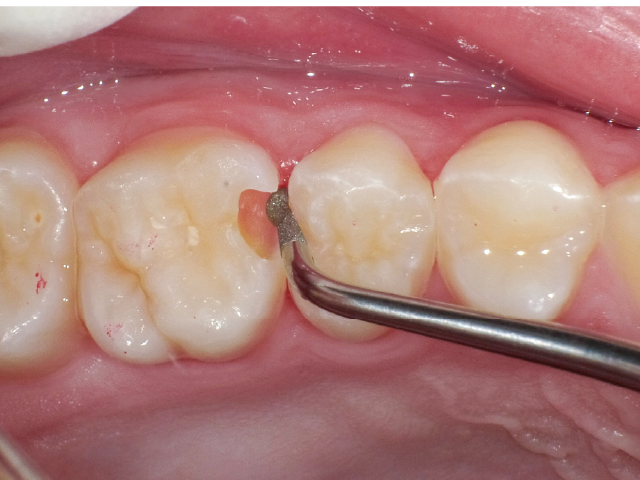

①窩洞形成段階(図1~7)

本症例では、ダイヤモンドの微粒子でコーティングされたエアースケーラーチップを窩洞形態の仕上げに使用。隣在歯の誤切削を防止し、エナメル質の切削断面を歯肉側窩縁までなめらかになるよう仕上げました。

本チップは切削時にストレスが少ない穏やかな振動のエアースケーラー専用のダイヤモンドチップで、切削部となる半球形状の面にのみダイヤモンド砥粒がコーティングされており、背面平坦部は隣在歯を削らないよう平滑になっています(図8、9)。チップの屈曲角度は110°に設定され、窩洞へのアクセスが容易な形状となっています。S67D(アングルの外側)、S68D(アングルの内側)チップは半球状の切削部位が設定され、臼歯部の近遠心両側の窩洞形成に使用が可能です。本症例では、左上6近心隣接面部の窩洞であったため、アングルの外側に半球状の切削部位が設定されている「S67D」を使用しました。これらの器具を使用することにより、頬舌側の隅角部歯質を温存した最小限の規模で窩洞形成を終了、防湿操作および隔壁の設置に移行することができました。